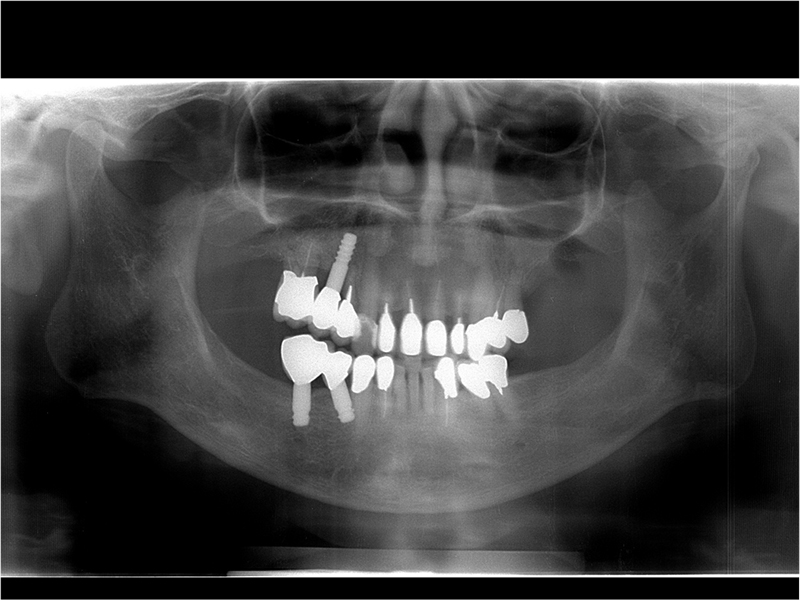

治療後のパントモ写真